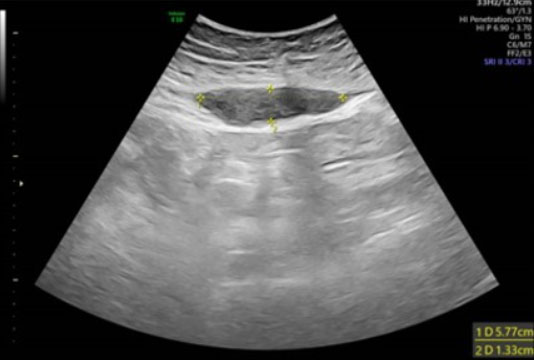

Figure 2: Postoperative day 3, rectus sheath hematoma on ultrasound (US). (A) Longitudinal view showing a subacute RSH hematoma—the hematoma is extended and mostly isoechoic compared to the surrounding tissue. (B) Transverse section of the same hematoma, showing the formation of hyperechoic septations within. Below the hematoma, the uterus and physiologic expanded endometrium are visible.